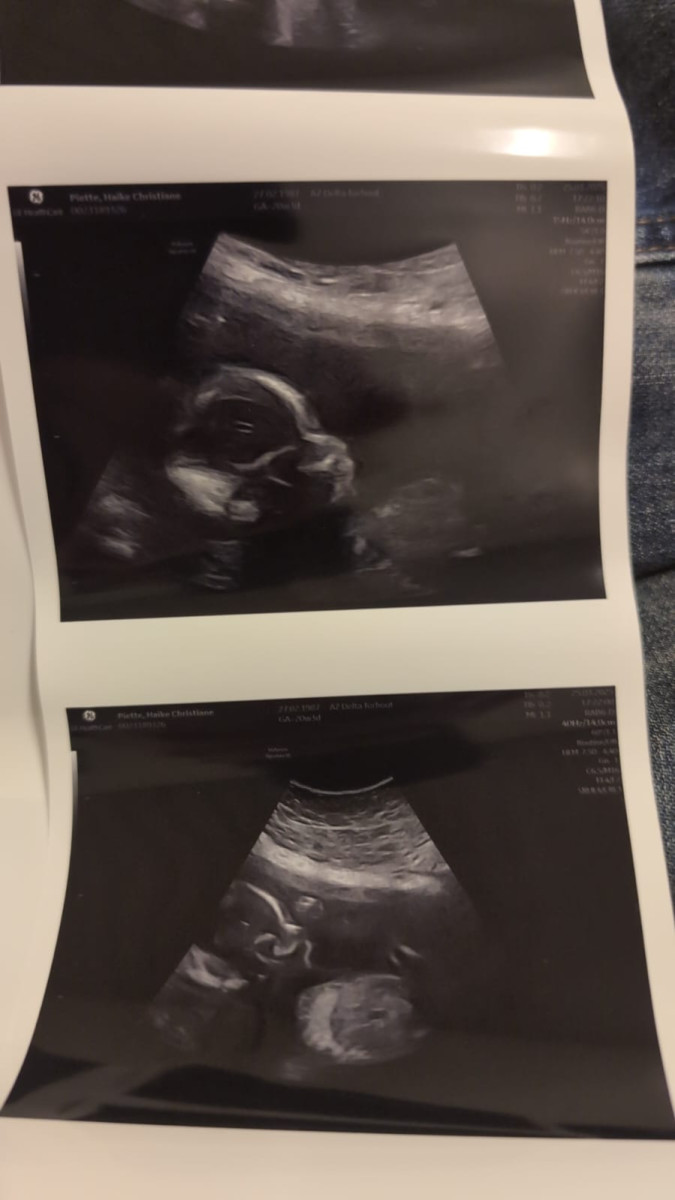

Toen we samen naar het scherm keken en de eerste beelden zagen van onze ongeboren dochter, werden we overspoeld door emoties. Daar was ze: klein, kwetsbaar, en al zo bijzonder. We zagen haar hartje kloppen en haar kleine lijfje bewegen. Wat ons vooral opviel, was hoe ze zich lekker had genesteld—ze lag heerlijk comfortabel, precies zoals zij dat wilde, en niet per se zoals de echoscopist het graag voor de foto had gezien.

Het was aandoenlijk om te merken dat ze nu al haar eigen willetje toont. In plaats van zich mooi in beeld te draaien, koos ze ervoor om lekker te blijven liggen zoals zij het fijn vond. Dat maakte het moment alleen maar specialer. We voelden ons nog meer verbonden met haar, en het besef dat we haar straks echt mogen ontmoeten, vervulde ons met blijdschap en verwachting.

We zijn in blijde verwachting en dankbaar dat we dit intieme, unieke moment samen mochten beleven. Met elke dag groeit niet alleen ons kindje, maar ook onze liefde en het verlangen om haar straks in onze armen te sluiten—precies zoals zij het zelf wil.